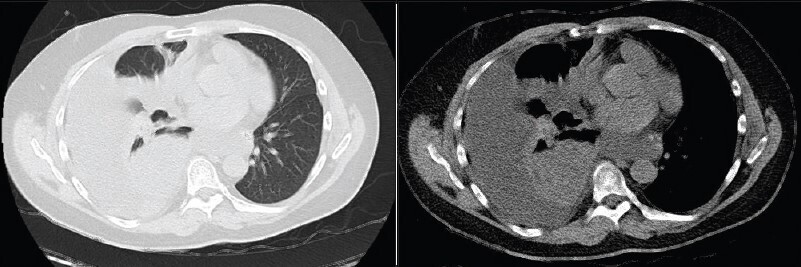

Vous n’observez pas de signe de lutte respiratoire, la dyspnée est silencieuse. L’auscultation pulmonaire retrouve une diminution du murmure vésiculaire à droite, accompagnée de sibilants localisés à mi-hauteur, la percussion révèle une matité. Les bruits du cœur sont réguliers, sans souffle. Il n’y a pas d’œdème des membres inférieurs, les mollets sont souples et indolores. Le reste de l’examen clinique est sans particularité.

Une embolie pulmonaire n’est pas une hypothèse que l’on peut éliminer par la clinique.

Le tableau clinique n’est pas évocateur d’un asthme : les sibilants sont localisés et non diffus, la dyspnée n’est pas bruyante, ni limitée au temps expiratoire. De plus, un asthme aigu grave se définit par un peak flow < 150 L/min ou < 50 % de la théorique, ce qui n’est pas le cas ici. Les sibilants peuvent être le signe d’une obstruction bronchique localisée.